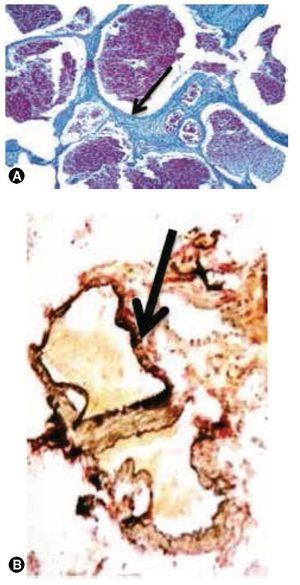

Se decide realizar resección de la lesión a través de un abordaje transulcar parietal izquierdo en el giro supramarginal, llegando al atrio del ventrículo lateral izquierdo, se identificó una lesión firme, violácea, de aproximadamente 3 x 3 cm de bordes regulares, multilobulada, se identificó un pedículo el cual se coaguló con bipolar y se extrajo la lesión en pieza única, enviándose a Patología, donde se reporta macroscópicamente un nódulo de 4.6 x 3.8 cm con superficie externa de aspecto fibroso, de color café grisáceo; al corte se observan bandas de fibrosis que rodean tejido color café rojizo de consistencia blanda. En el examen microscópico corresponde a una malformación vascular, compuesta por vasos sanguíneos de distintos calibres y con espesor aumentado debido al depósito de colágeno tipo I (colágeno maduro) que se hace más evidente con la tinción especial de tricrómico de Masson; se realizó la tinción de fibras elásticas (tinción de Verhöeff) en el que se hace evidente la presencia de la capa elástica en los elementos arteriales de la lesión. El diagnóstico definitivo histopatológico es de MAV (figs. 2, 3 y 4).

Figura 2 A). Pieza quirúrgica de 3 cm de eje mayor, corresponde a montaje de la lesión teñida con técnica de hematoxilina & eosina; es bien delimitada constituida por múltiples conductos vasculares confluentes y congestivos, de calibre y espesor de pared variables. B) El componente principal de las paredes vasculares es tejido conjuntivo denso regular rico en colágeno tipo I tricrómico de Masson, tejido que también delimita la lesión sin formar una cápsula verdadera.